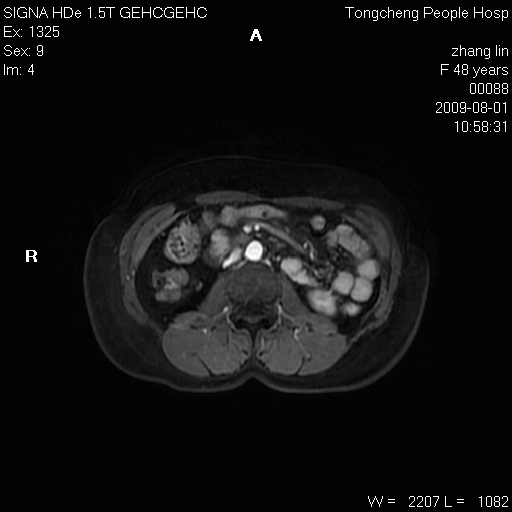

女,48岁。健康体检,彩超发现右肾占位性病变。平素健康。

临床诊断:右肾占位性病变,性质待定(囊肿?肿瘤?)。

上中腹部mr平扫+增强扫描,图像如下:

右肾上极见一类圆形病灶,t1wi呈等信号t2wi呈等高混杂信号,三期增强无强化,边界清---考虑囊肿出血。

同反相位均表现为等信号,病变无强化,考虑含蛋白的囊肿可能,弥散加权相或许有些帮助,